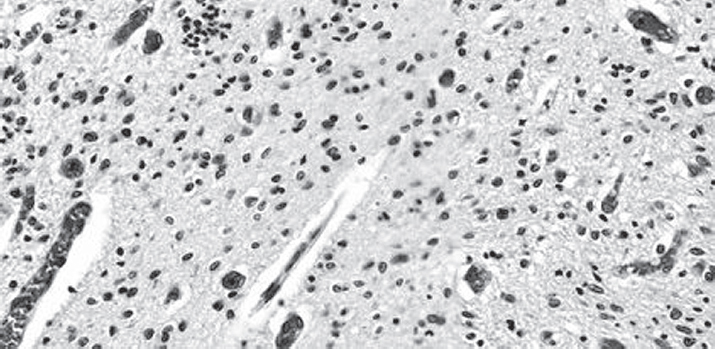

На примере клинического случая рассмотрены морфологические особенности кровоизлияния в боковые желудочки головного мозга у ребенка, родившегося с экстремально низкой массой тела. Приведено детальное описание морфологии повреждения герминативного матрикса и сосудистого сплетения как одних из самых частых источников кровоизлияния. Наибольшее внимание уделено состоянию кровеносных сосудов микроциркуляторного русла. Указаны возможные причины и последствия сосудистого повреждения перивентрикулярной области. Научные работы последних лет, направленные на изучение патогенеза внутрижелудочковых кровоизлияний, свидетельствуют, что у детей, родившихся в 37 нед. гестации и позже, внутрижелудочковые кровоизлияния возникают чаще вследствие повреждения сосудистого сплетения. В приведенном случае обращает на себя внимание кровоизлияние из сосудистого русла редуцирующегося герминативного матрикса в субэпендимальную область с распространением в собственно вещество головного мозга и выходом крови непосредственно в полости боковых желудочков.